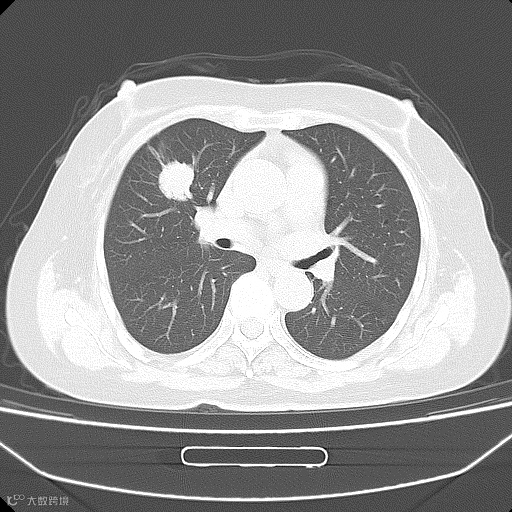

这是她的胸部CT,很明显,右肺上叶有一个结节!而这个病灶,在胸片上竟然完全看不到。后来这个病人做了CT引导下的穿刺活检,病理诊断为中分化腺癌。